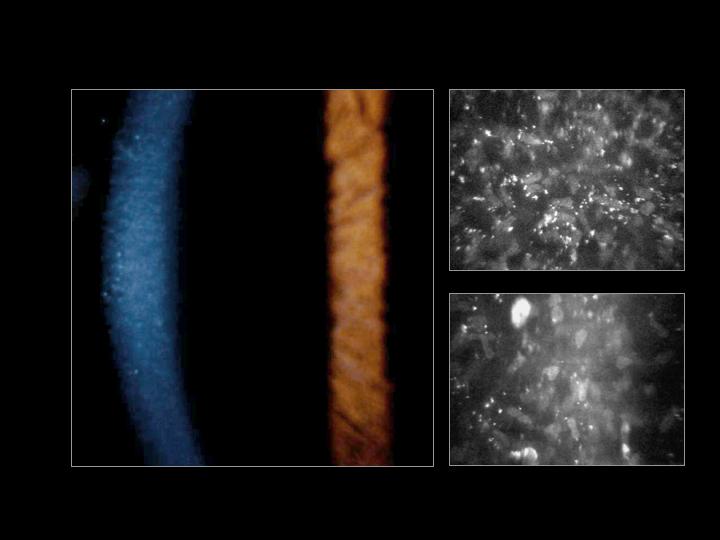

문자그대로 주근깨와 같은 작은 혼탁이 기질에만 존재하는 질환입니다.

작은 혼탁이 상피는 침범하지 않으며, 기질의 전층에 발생합니다.

미세한 회색 얼룩이 양측 각막의 전층에 발생하게되며,

과립은 lipid 또는 glycosaminoglycan이 리소좀 내에 축적되어 형성된 것으로 추정되며,

조직학적으로는 PAS 양성 및 Sudan-positive deposits가 보입니다.